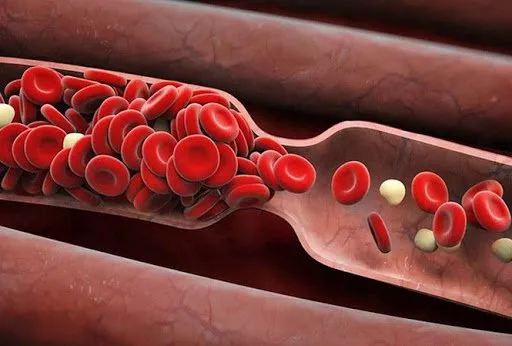

Bài viết cung cấp thông tin về các loại thuốc chống đông được sử dụng trong điều trị huyết khối tĩnh mạch sâu chi dưới, thời gian điều trị và những thận trọng cần lưu ý khi sử dụng thuốc. Việc tuân...

Bài viết cung cấp thông tin về các loại thuốc chống đông được sử dụng trong điều trị huyết khối tĩnh mạch sâu chi dưới, thời gian điều trị và những thận trọng cần lưu ý khi sử dụng thuốc. Việc tuân...